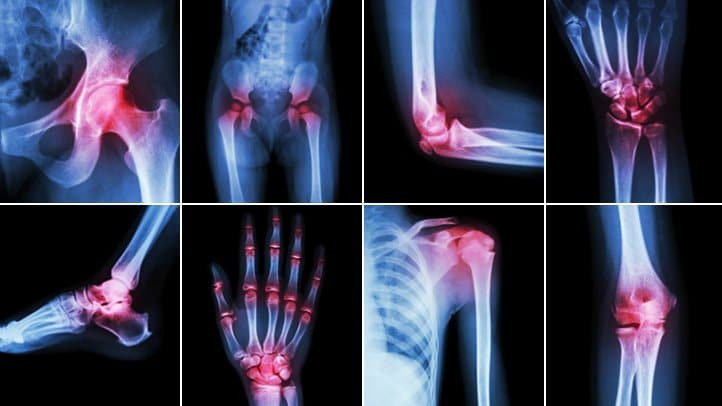

관절염은 말 그대로 관절에 염증이 생기는 질환을 통칭합니다. 관절이란 뼈와 뼈가 만나는 부위인데 이 부위에 염증이 생기면 통증, 뻣뻣함, 부기, 운동 제한 등 다양한 증상이 나타납니다.

관절염은 생각보다 종류가 매우 다양합니다. 대표적인 관절염 유형을 소개할게요.

퇴행성 관절염 (골관절염, Osteoarthritis)

가장 흔한 관절염 유형

연골이 닳아 뼈끼리 마찰되며 통증 유발

주로 무릎, 고관절, 손가락 등에 발생

류마티스 관절염 (Rheumatoid Arthritis)

자가면역질환의 일종

손가락, 손목 등 작은 관절부터 시작되어 양쪽 대칭으로 통증 발생

조조강직(아침 뻣뻣함)이 대표 증상